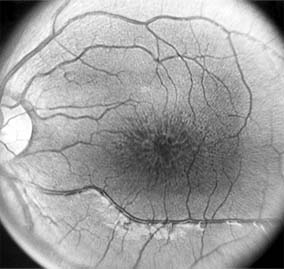

Central serous chorioretinopathy is characterized by serous detachment of the sensory retina as a consequence of focal leakage of fluid from the choriocapillaris through a defect in the retinal pigment epithelium (Figures 10-2 and 10-3). This disease typically affects young to middle-aged men and may be related to life stress events. Most patients present with the sudden onset of blurred vision, micropsia, metamorphopsia, and central scotoma. Visual acuity is often only moderately decreased and may be improved to near-normal with a small hyperopic correction.

Figure 10-2

Figure 10-2: Central serous chorioretinopathy with sensory retinal detachment (arrows) extending into the fovea.

Figure 10-3

Figure 10-3: Fluorescein angiogram of central serous chorioretinopathy shows active disease with both a retinal pigment epithelial detachment (small arrows) and a sensory retinal detachment (large arrows). Two foci of inactive disease (open arrows) are also present.